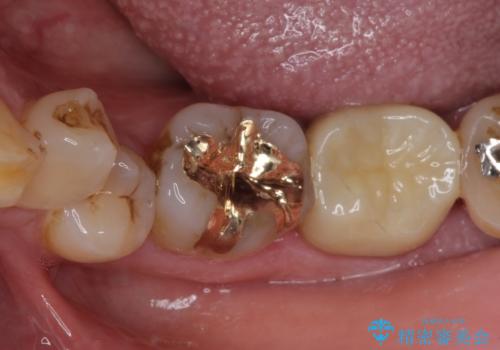

咬合力が著しく強いため、欠損の多い歯はフルジルコニアクラウンへ、その他の虫歯はゴールドインレー(PGAインレー)にて修復することとしました。

来院時は全てセラミックでの治療を希望されていましたが、歯列や咬み合わせから咬合力による破損リスクが高いと判断されたため、ゴールドインレーを選択しました。